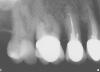

конфьюзд Опубликовано 1 мая, 2007 Поделиться Опубликовано 1 мая, 2007 Может он просто почту раз в неделю смотрит, вот и не ответил. Если,как вы говорите, врач хороший, то он вам так вкладку поставит, что вы про нее забудете лет на 10 - 15. Хороший или нет - я не знаю. Мне только показалось, что неплохой. А лечение он начинает с 17, который меня вообще не беспокоит ( на снимке 16 под коронкой и рядом 17), у меня с 16 проблемы из-за плохой коронки, а 17-й, может быть, лучше вообще не трогать (?). Вдруг он мне его разфигачит и депульпацию предложит. Начал бы с проблемного зуба - я бы меньше волновалась. А то что плохой церек или хороший, целесообразно так много пилить или нет - это больше наши с коллегами разногласия - мы будем спорить до хрипоты и навряд ли придем к чему либо одному. Мне бы больше доктор подошел который мало пилит (только где необходимо), а качество очень высокое. Как вы думаете, есть такие или все пилить хотят? Это правда, что с помощью лазера и без сверления можно обойтись? Выровнять и отодвинуть конечно можно, только я бы не стал. Наверное дешевле снять эту корнку, полечить 38 и поставить коронку новую. Не только по деньгам дешевле, но и для вас проблем меньше будет Проблем с лечением больше? А как относительно прогноза на будущее? Как хорошо, что есть этот форум! Спасибо большое Вам всем за участие Ссылка на комментарий

Мартовский Опубликовано 2 мая, 2007 Поделиться Опубликовано 2 мая, 2007 (изменено) Про лазер здесь уже достаточно написали - посмотрите в разделе "врачам". По поводу последнего снимка - я бы лечил одновременно оба зуба. Создать контактный пункт с коронкой довольно затруднительно, да и незачем, если все равно ее снимать. Снял бы коронку, восстановил 17, потом бы спокойно лечил каналы 16 это все в первое посещение. Допускаю что у вашего врача другой взгляд на это, ну а так же что вы опять что-то не допоняли либо он недообъяснил Изменено 2 мая, 2007 пользователем Мартовский Ссылка на комментарий

конфьюзд Опубликовано 2 мая, 2007 Поделиться Опубликовано 2 мая, 2007 Про лазер здесь уже достаточно написали - посмотрите в разделе "врачам". По поводу последнего снимка - я бы лечил одновременно оба зуба. Создать контактный пункт с коронкой довольно затруднительно, да и незачем, если все равно ее снимать. Снял бы коронку, восстановил 17, потом бы спокойно лечил каналы 16 это все в первое посещение. Допускаю что у вашего врача другой взгляд на это, ну а так же что вы опять что-то не допоняли либо он недообъяснил Я хотела лечить 16-й у эндодонта так как каналы сложные (снять коронку и пройти каналы), но стоматолог сказал невнятно (больше мимикой чем словами) что не нужно и я отменила лечение у эндодонта (боялась что-то делать без его согласия). Может действительно причина моего дискомфорта в 17. Опять таки, он не объяснил все толком, а я поняла, что вкладку он делает лишь потому, чтоб восстановить правильную форму зуба. Можете ли вы мне сказать, есть ли у меня вторичный кариес под пломбой в 17-ом и какова вероятность необходимости депульпирования? Ссылка на комментарий

Мартовский Опубликовано 2 мая, 2007 Поделиться Опубликовано 2 мая, 2007 (изменено) Я хотела лечить 16-й у эндодонта так как каналы сложные (снять коронку и пройти каналы), но стоматолог сказал невнятно (больше мимикой чем словами) что не нужно и я отменила лечение у эндодонта (боялась что-то делать без его согласия). Может действительно причина моего дискомфорта в 17. Опять таки, он не объяснил все толком, а я поняла, что вкладку он делает лишь потому, чтоб восстановить правильную форму зуба. Можете ли вы мне сказать, есть ли у меня вторичный кариес под пломбой в 17-ом и какова вероятность необходимости депульпирования? Если темное пятно в пришеечной области на контакте с коронкой это кариозная полость, то она сообщается с полостью зуба и придется депульпировать. Точнее сказать не могу - качество снимка не позволяет. А про эндодонтов - моя не понимает. Я все сам делаю Изменено 2 мая, 2007 пользователем Мартовский Ссылка на комментарий